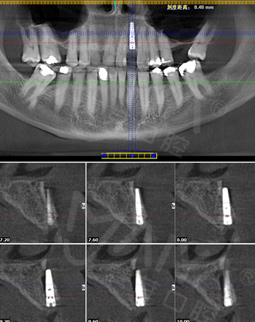

今年的4月18日,我去了第一次复诊后,直接飞回了加拿大。坐飞机过程也没有什么不适感,而且有按照郑院长的要求,一直在好好的呵护我的种植牙。现在回到中国,手机上显示客服的复诊短信提醒,虽然在还未种完牙的情况下,但这丝毫不影响我继续享用美食。复诊的时候,拍了片子,郑院长说植入的植体与骨结合不错,然后给我安装了愈合基台,说我有什么不适的话,都可以过来。

2016年4月 牙槽骨严重缺损,不适合一期种牙

来到深圳,多方寻医,一个医生朋友告诉我,这个只有到麦芽找郑苍尚院长,他能做。“我有6个月一直没有牙齿,我要我的牙齿。”这是我见到郑院长后说的第一句话,在麦芽流程很顺利,经过拍片检查后,郑院长说我剩余残根反复发炎松动,牙槽骨受损严重,影响咀嚼功能,只能拔除残根后需引导骨组织再生,不能一期种牙....很专业的词我不太懂,但是他能处理我就放心了!

在郑院长的建议下,我选择了诺贝尔植体,种植牙还需要骨粉骨膜,大致了解了种牙的流程,我很满意。